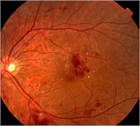

1. 虚血型の網膜静脈分枝閉塞症(BRVO)では、虚血網膜で産生される血管新生サイトカイン、VEGFの影響で、発症後数年以内に、網膜血管から硝子体に立ち上がるNVを生じて硝子体出血を生じる危険性がある。200~500μmの凝固径で1凝固斑の間隔をあけて虚血網膜部位を覆う散発凝固scatter photocoagulationはVEGFの発生母地を破壊し、NV発生を抑制する。治療時期はNVの発生を確認した時点でよいとされている(推奨度1)